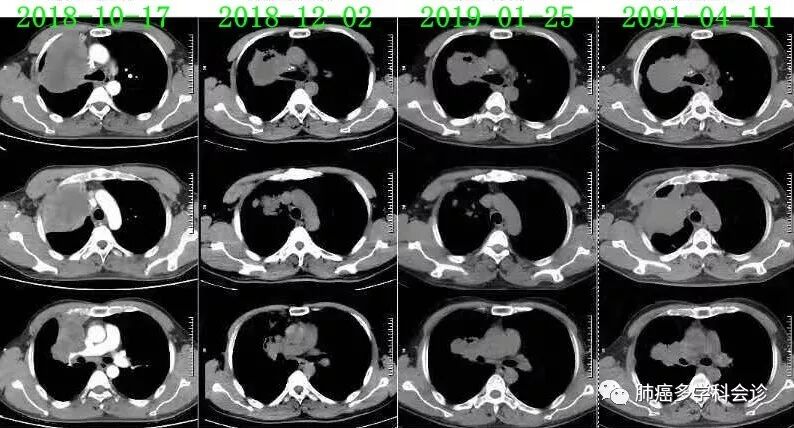

2018.10.28 - 2019.03.22,在呼吸科接受一线化疗:“吉西他滨+奈达铂”× 6周期,最佳疗效PR。2019-04-11复查CT,示疾病进展:

- 【多学科会诊病例】 以下为一位肺鳞癌患者经过二个方案化疗后,疾病进展、不耐受继续化疗。三线“PD-1抗体+安罗替尼”治疗, 2周期后肿瘤明显缩小: 患者郑WD,男,46岁,吸烟20余年,平均20支/